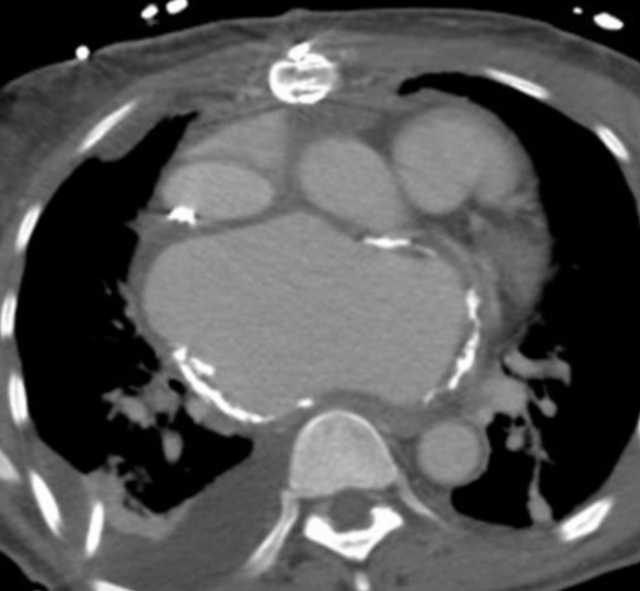

Mitral Stenosis (most commonly in setting of rheumatic heart disease)

high pressures from the stenosis cause calcification of the left atrium

(mitral calcs in the setting of LA enlargement are suggestive of the same pathology)

Dx from mitral regurgitation by absence of LV dilatation